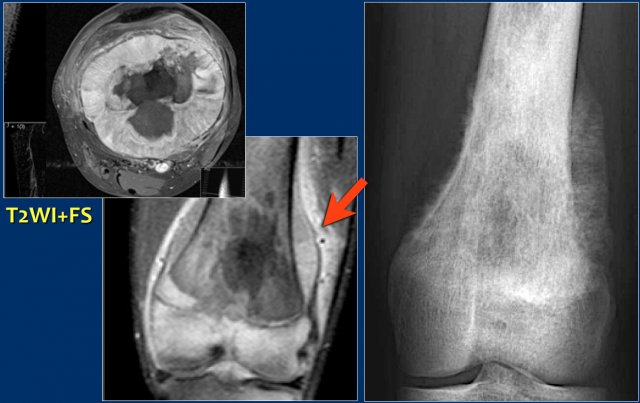

Here images of a 30-year-old male.

There is a wel-defined lytic lesion of the olecranon with several ridges and a pathologic fracture.

The differential diagnosis includes giant cell tumor and ABC.

The T2WI+FS shows fluid-levels due to sedimentation making ABC the most likely diagnosis.

Biopsy however revealed Brown tumor.